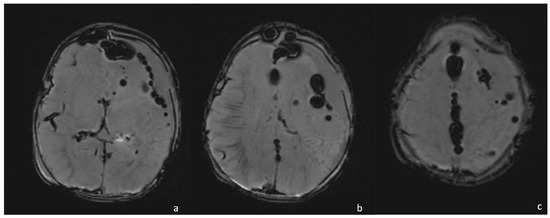

- Late capsule formation (weeks to months): The parenchymal abscess presents a necrotic core, appearing hypointense on T1WI and hyperintense on T2WI with diffusion restriction on DWI/ADC. The capsule is inhomogeneously thick, appearing thicker towards the cortex and thinner towards the ventricles, appears isointense on T1WI and hypointense on T2WI, and presents an intense enhancement. On the US, the abscess presents a well-defined hypoechoic core and a complete hyperechoic rim, pairing CT that shows a well-defined hypodense core and a complete peripheral enhancement.